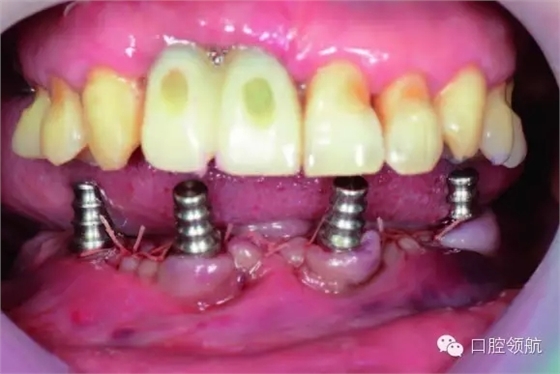

由于三組金屬烤瓷橋重度松動,術(shù)中未經(jīng)過分冠將三組固定橋連同橋基牙拔除。拔除后徹底搔刮根尖部肉芽組織并切除牙頸部發(fā)炎牙齦組織。因為后部牙槽骨基本光滑平整,因此只在前牙區(qū)做少量骨修整。

植入4顆NobelActive™,后部為RP4.3*15,前部為RP4.3*13。安放閉口轉(zhuǎn)移桿(圖6-9,圖6-10)。

圖6-9 術(shù)中拔除10顆患牙

圖6-10 下頜植入All-on-4 后口內(nèi)照